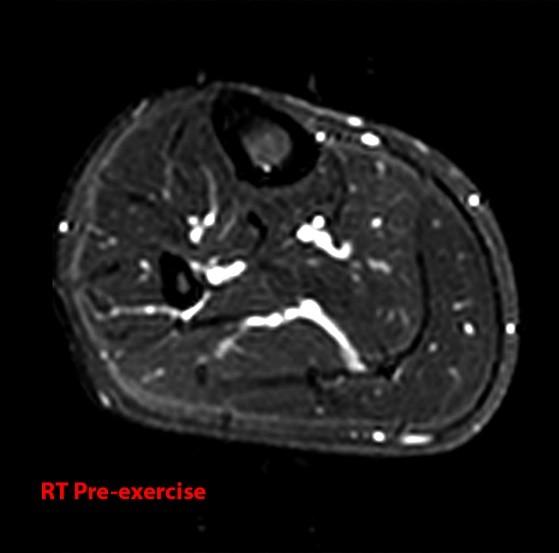

From radsource.us

Compartment Syndrome of the Leg Radsource Leg Pain Compartment Syndrome Leg compartment syndrome is a devastating lower extremity condition where the osseofascial compartment pressure rises to a level that decreases perfusion to the leg. Compartment syndrome is a surgical emergency characterised by increased pressure within a closed space. Acute compartment syndrome (acs) of the lower leg is a time sensitive limb threatening surgical emergency. The legs, arms, forearms, thighs, feet,. Leg Pain Compartment Syndrome.

Compartment Syndrome of the Leg Radsource Leg Pain Compartment Syndrome Compartment syndrome is a surgical emergency characterised by increased pressure within a closed space. Compartment syndrome is an increase in pressure inside a muscle, which restricts blood flow and causes pain. It is usually encountered in limb injuries. Leg compartment syndrome is a devastating lower extremity condition where the osseofascial compartment pressure rises to a level that decreases perfusion to. Leg Pain Compartment Syndrome.